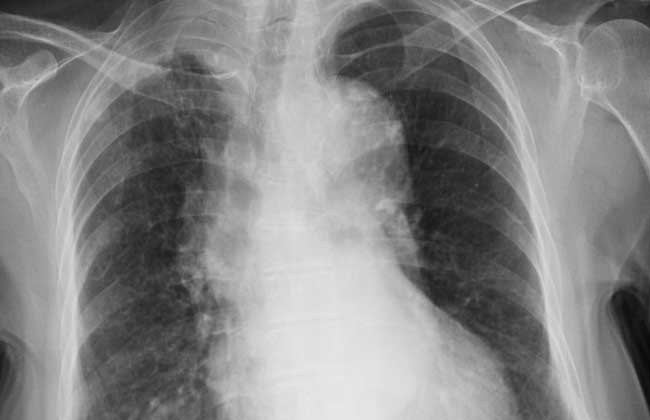

结核性胸膜炎是否具有传染性主要还要看是由何种原因而引发的,引发结核性胸膜炎的病因很多。如果不是肺结核引发的则不会传染,这是因为胸膜没有对外通道,是封闭的。如果是肺结核引起的,那么就会通过肺部对外传染。建议大家如陪同家人就诊时或外出时,需戴上口罩,以免细菌侵入自己的体内,造成更多疾病隐患,危及自己及家人的健康。